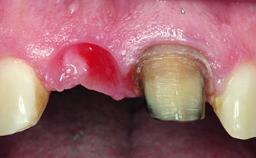

Replacement of a Missing Upper Left Central Incisor: Late Placement of an RC Bone Level Implant, CAD/CAM Zirconia Abutment

Eduardo R Lorenzana, Jason R Gillespie

A healthy 37-year-old female patient was referred for a consultation on the replacement of missing tooth 21 with an implant-supported restoration. She stated that several years previously the tooth had been traumatically avulsed following a motor vehicle accident. The tooth was replaced with a three-unit fixed partial denture (FPD) immediately afterwards. Over time, she became disillusioned with the FPD and looked for a different option, including orthodontic therapy. She presented still in her orthodontic appliances, with the pontic sectioned free from the FPD but attached to the archwire. Her orthodontist felt that orthodontic treatment had been successfully completed, but nevertheless referred her before removing the appliances in case adjustments were necessary.